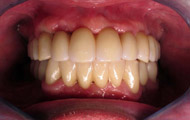

Exemple d’une réhabilitation complète implantaire

Situation clinique initiale

Situation clinique terminée